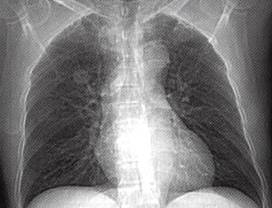

图1肺错构瘤

A.X线胸片示右上肺野孤立结节,边缘光整;